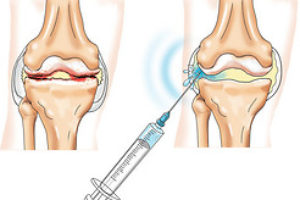

Rheumatology is the branch of medicine that deals with diagnosis and treatment of a number of systemic diseases of connective tissue, which affects the joints, blood vessels, heart, gastrointestinal …